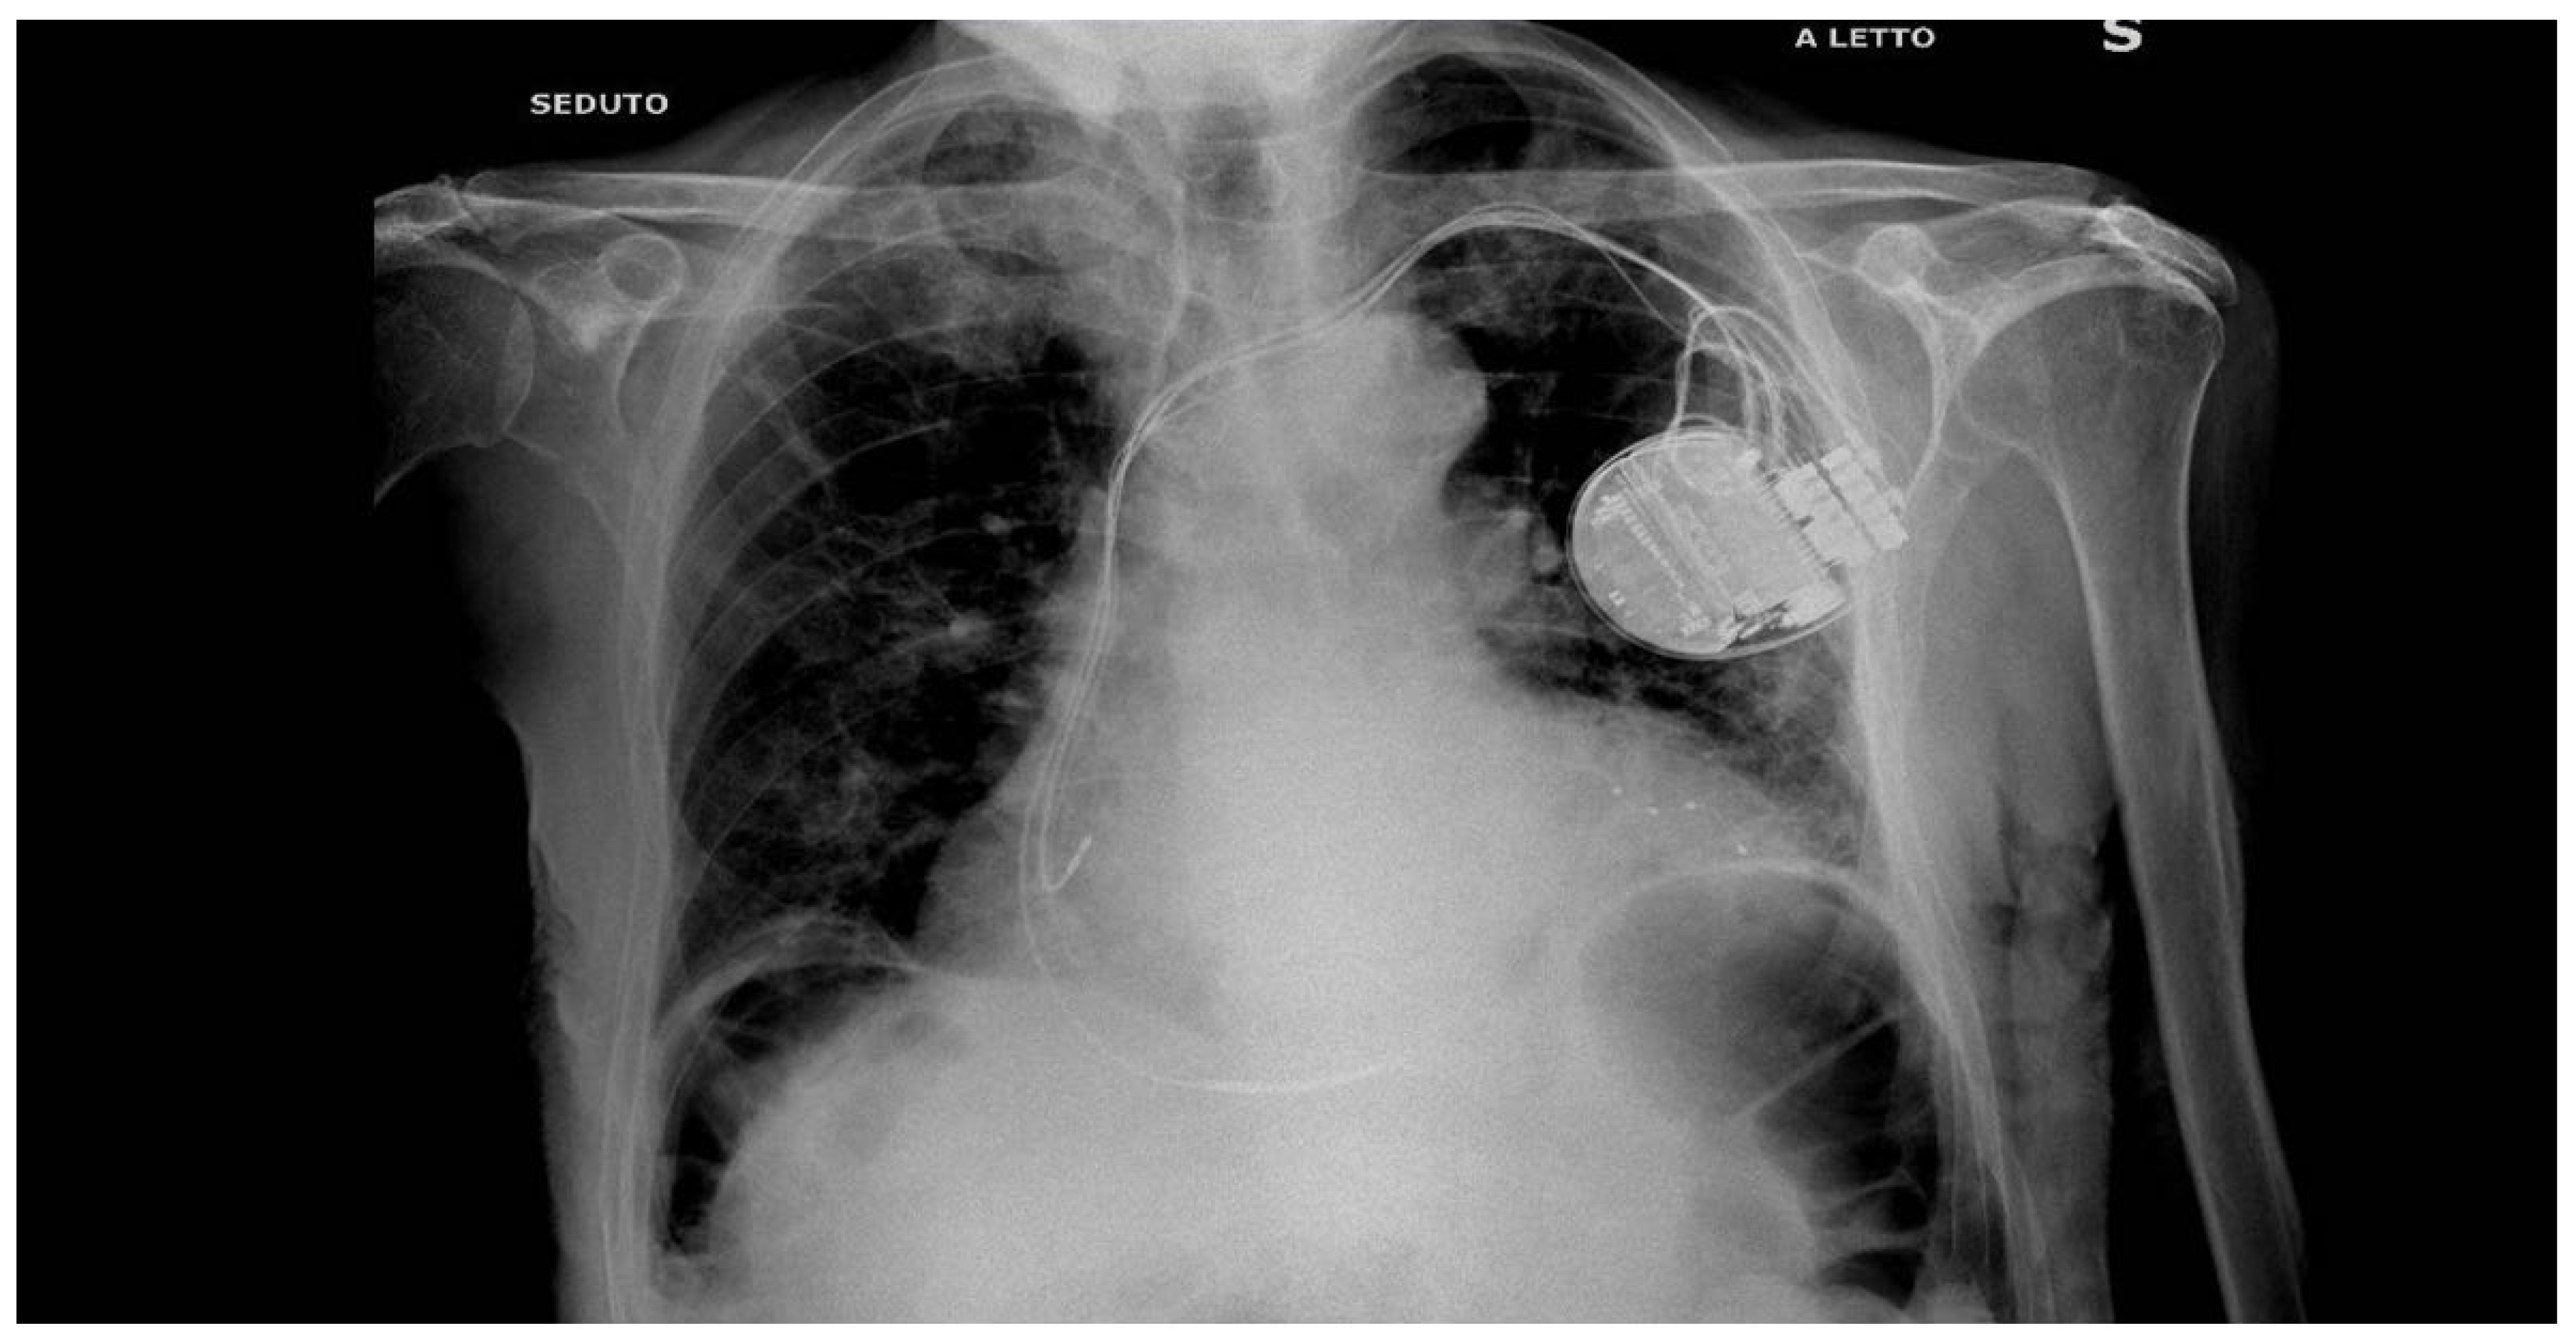

2. Case Presentation